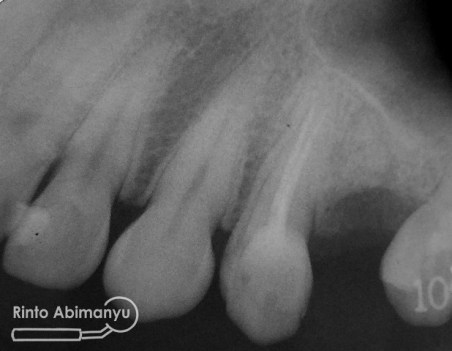

Tampilan setelah pengisian…

Untuk coronal seal memakai low shrinkage stress flowable composite SDR (Dentsply) dan atasnya ditutup dengan komposit packable….

Pengambilan ronsen dilakukan pada gigi tersebut…